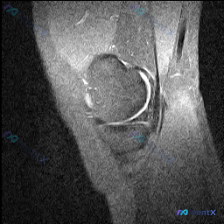

这份是膝关节矢状位MRI图像,属于T2加权/质子加权压脂序列,图像分辨率低、噪声大,仅能显示髌骨、股骨远端前部、胫骨近端前部和髌股关节局部区域,无法判断是内侧还是外侧层面。

- 关节软骨:髌股关节面软骨信号尚可,未见明确剥脱改变,但图像质量限制无法评估微小损伤,报告提示存在软骨异常

- 髌下脂肪垫(Hoffa脂肪垫):这个区域是本病例的重点,髌骨下方的脂肪垫信号不均匀,可见局部高信号影;髌腱走行正常,无增厚或中断

- 关节滑膜与积液:髌上囊可见明显液体高信号,提示存在关节积液